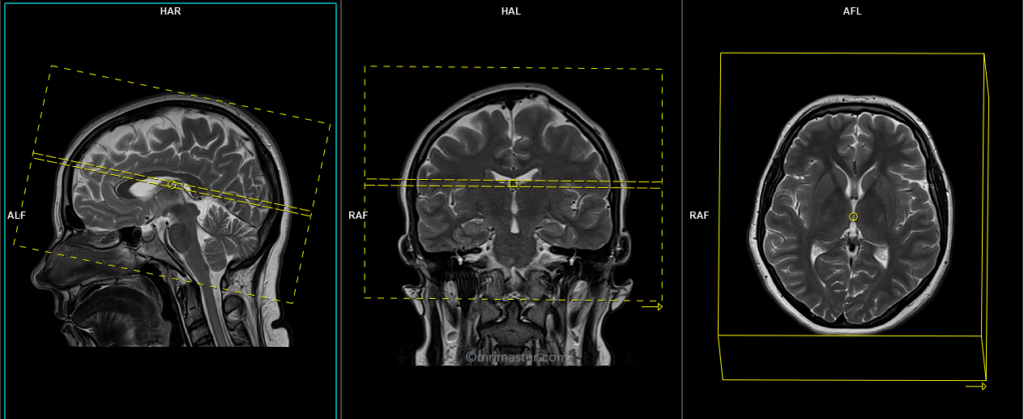

T2 tse axial

Plan the axial slices on the sagittal plane and position the block parallel to the genu and splenium of the corpus callosum. Verify the planning block in the other two planes and ensure that an appropriate angle is maintained in the coronal plane, making it perpendicular to the line of the midline of the brain and the 4th ventricle. Ensure that the number of slices is sufficient to cover the entire brain from the vertex to the line of the foramen magnum.

Protocol Parameters of T2

TR 4000-5500 | TE 100-120 | SLICE 3MM | FLIP 130-150 | PHASE R>L | MATRIX 320X320 | FOV 210-230 | GAP 10% | NEX(AVRAGE) 2 |

T1 SE coronal

Plan the coronal slices on the sagittal plane and angle the planning block perpendicular to the line along the genu and splenium of the corpus callosum. Verify the planning block in the other two planes. Ensure that an appropriate angle is maintained in the axial plane, perpendicular to the midline of the brain. The number of slices should be sufficient to cover the entire brain from the frontal sinus to the line of the occipital protuberance.

Protocol Parameters of T1

TR 500-700 | TE 15-25 | SLICE 3MM | FLIP 90 | PHASE R>L | MATRIX 304X304 | FOV 210-230 | GAP 10% | NEX(AVRAGE) 2 |

T2 tse sagittal

Plan the sagittal slices on the axial plane and position the block parallel to the midline of the brain. Verify the planning block in the other two planes. Angle the planning block appropriately in the coronal plane, ensuring it is parallel to the line along the midline of the brain and the 4th ventricle. Make sure that the number of slices is sufficient to cover the entire brain from one temporal lobe to the other.

Protocol Parameters of T2 Sagittal

TR 4500-6000 | TE 100-120 | SLICE 3MM | FLIP 130-150 | PHASE A>P | MATRIX 320X304 | FOV 210-230 | GAP 10% | NEX(AVRAGE) 2 |